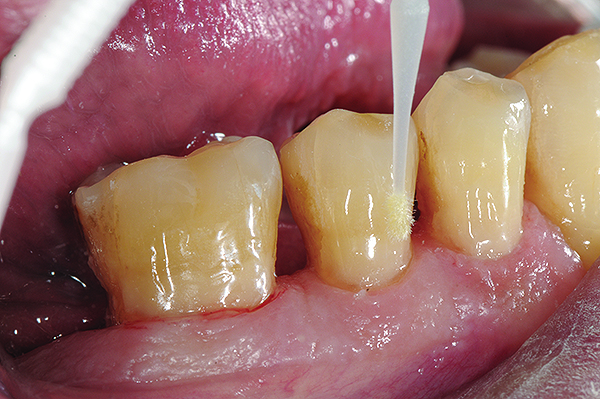

Fig 6. In Case 2, pretreatment view of multiple non-carious cervical lesions.

Figure 6

Fig 7. Cavities were cleaned with 20% polyacrylic acid solution.

Figure 7